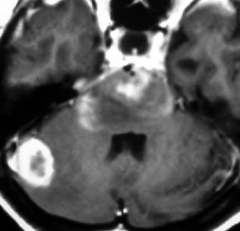

4歳の時に低線量頭蓋照射を受けていますが,医療関係の仕事について自立していた33歳の女性です。仕事中に記憶が飛ぶという症状がでて,周囲からおかしいと言われて受診しました。右の扁桃体のところ(左側のMRI)に海綿状血管腫ができていて,側頭葉てんかん(欠伸発作)を生じていました。バルプロ酸の投与で発作は止まって職場復帰しています。